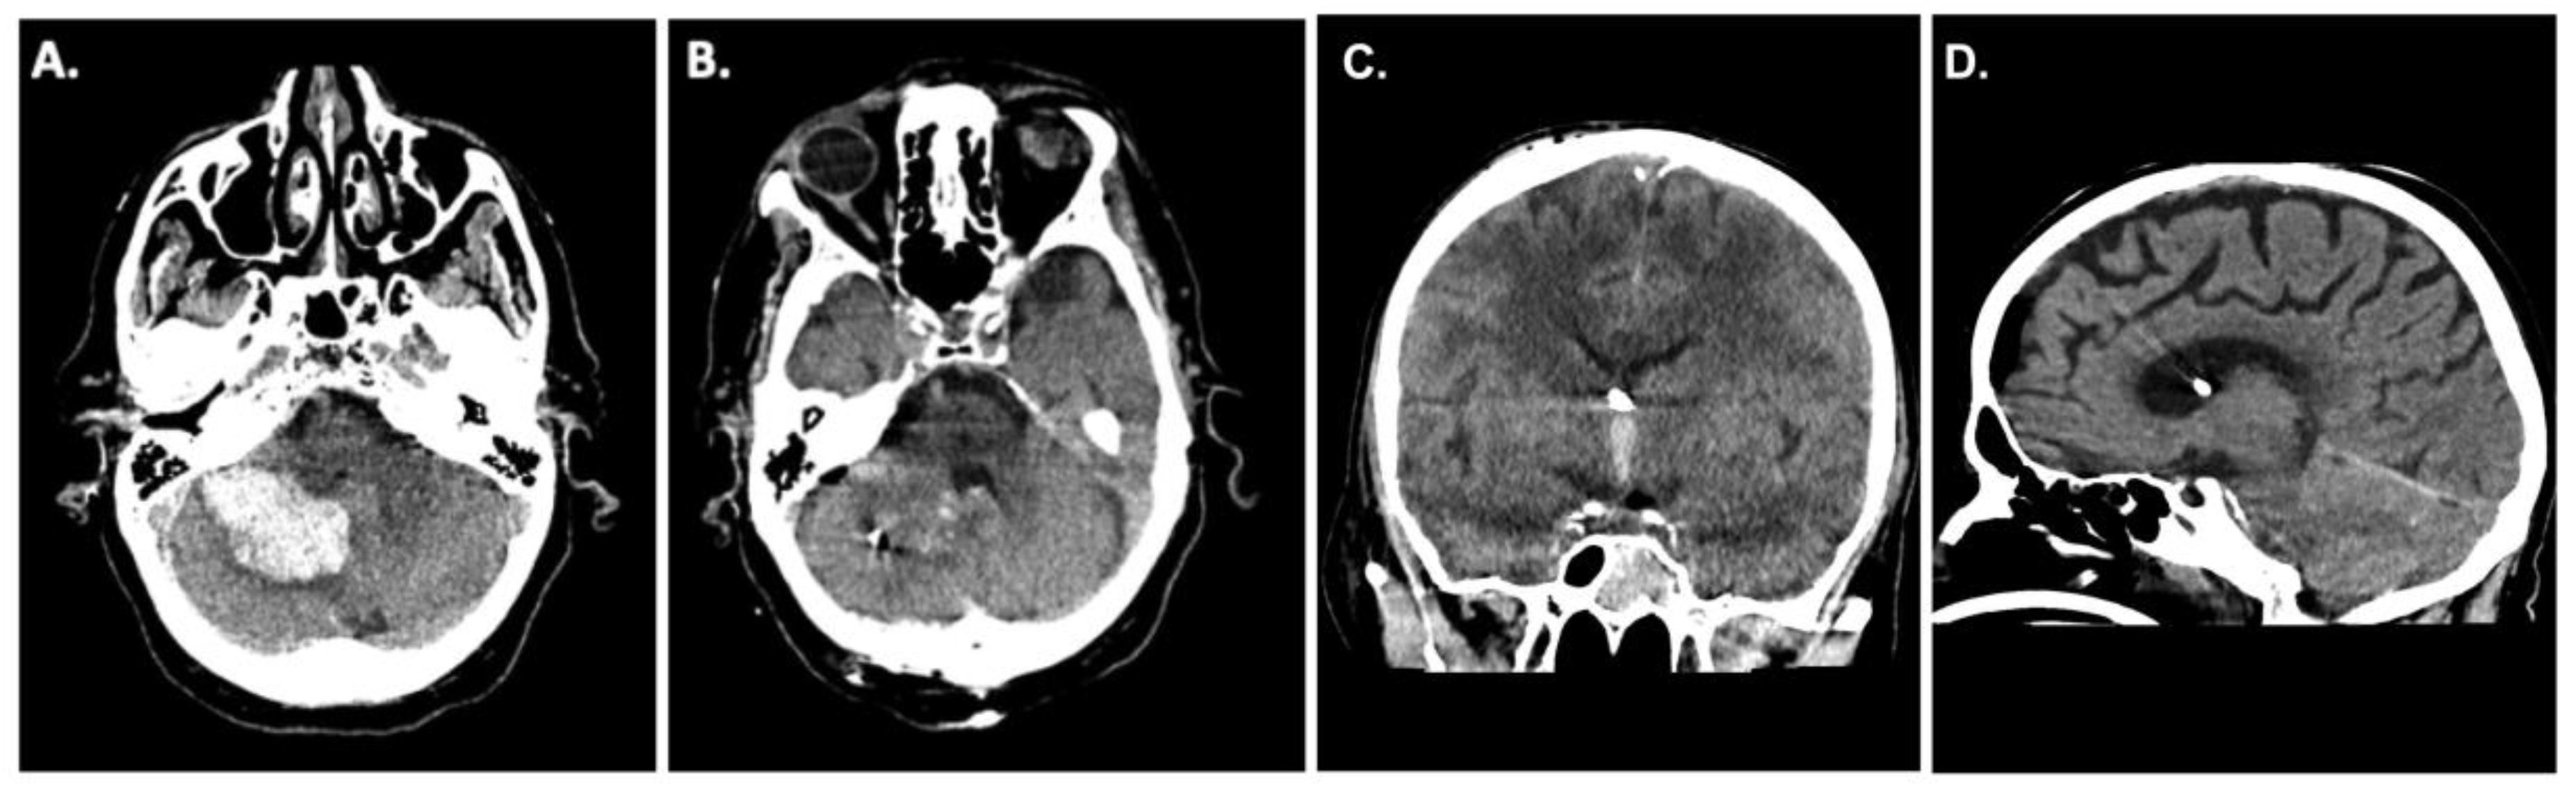

A 62-year-old patient presented to the emergency room at our institution after collapsing. Due to worsening mental status he was electively intubated and a computed tomography (CT)-scan of the brain revealed a cerebellar hemorrhage with compression of the fourth ventricle/resultant hydrocephalus (Figure 1A). CT angiography failed to demonstrate any underlying vascular pathology. Due to the size of the hemorrhage and its mass effect, the patient was taken for an emergency clot evacuation and surgical decompression. Just prior to the decompression a combined external ventricular drain-ICP probe from Spiegelberg was placed in the right frontal ventricle; the sub-occipital craniotomy with hematoma evacuation was uncomplicated. During the case an additional infratentorial ICP probe was inserted in the hematoma cavity as per our institutional standard. After replacing the bone, the infratentorial probe exhibited an ICP value of 27mmHg whilst the supratentorial probe reported 13mmHg, respectively. Despite several attempts to re-zero, the infratentorial ICP value did not change. As such, we felt it was prudent to explore the surgical site yet upon reopening the surgical field showed no sign of rebleeding and/or massive swelling of the cerebellum. Even the cerebellum was under the level of the dura, which was discordant to the elevated ICP value of 27mmHg. We removed the ICP sonde and a new ICP probe was inserted into the cerebellum (Figure 1B). Observing the previous ICP probe, we noticed a thin clot adhering to the air-pouch of the ICP probe. After revising the probes position, the infratentorial ICP was noted to be 15mmHg. The postoperative CT scan showed sufficient hematoma evacuation with proper location of the combined EVD-ICP probe in the right ventricle (Figure 1B/1C). In addition, there was no sign of transtentorial herniation in the postoperative CT-scan (Figure 1D). The remainder of the patients post-operative course was uneventful and they were ultimately discharged to a rehabilitation facility given residual imbalance and dysmetria.

Figure 1. A. Preoperative CT scan with the diagnosis of a spontaneous cerebellar hemorrhage on the right side. B. CT scan after hematoma evacuation and insertion of a Spiegelberg 3-PN sensor in the cerebellar parenchyma on the right side.